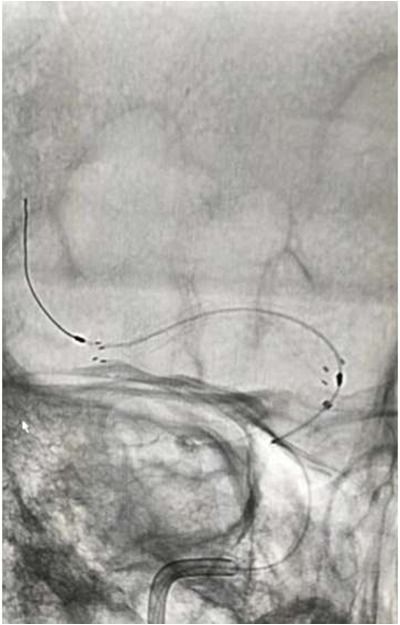

导丝导管通过闭塞部位,经微导管造影,证实在远端真腔内,取栓后M1重度狭窄,球囊扩张。

球囊扩张